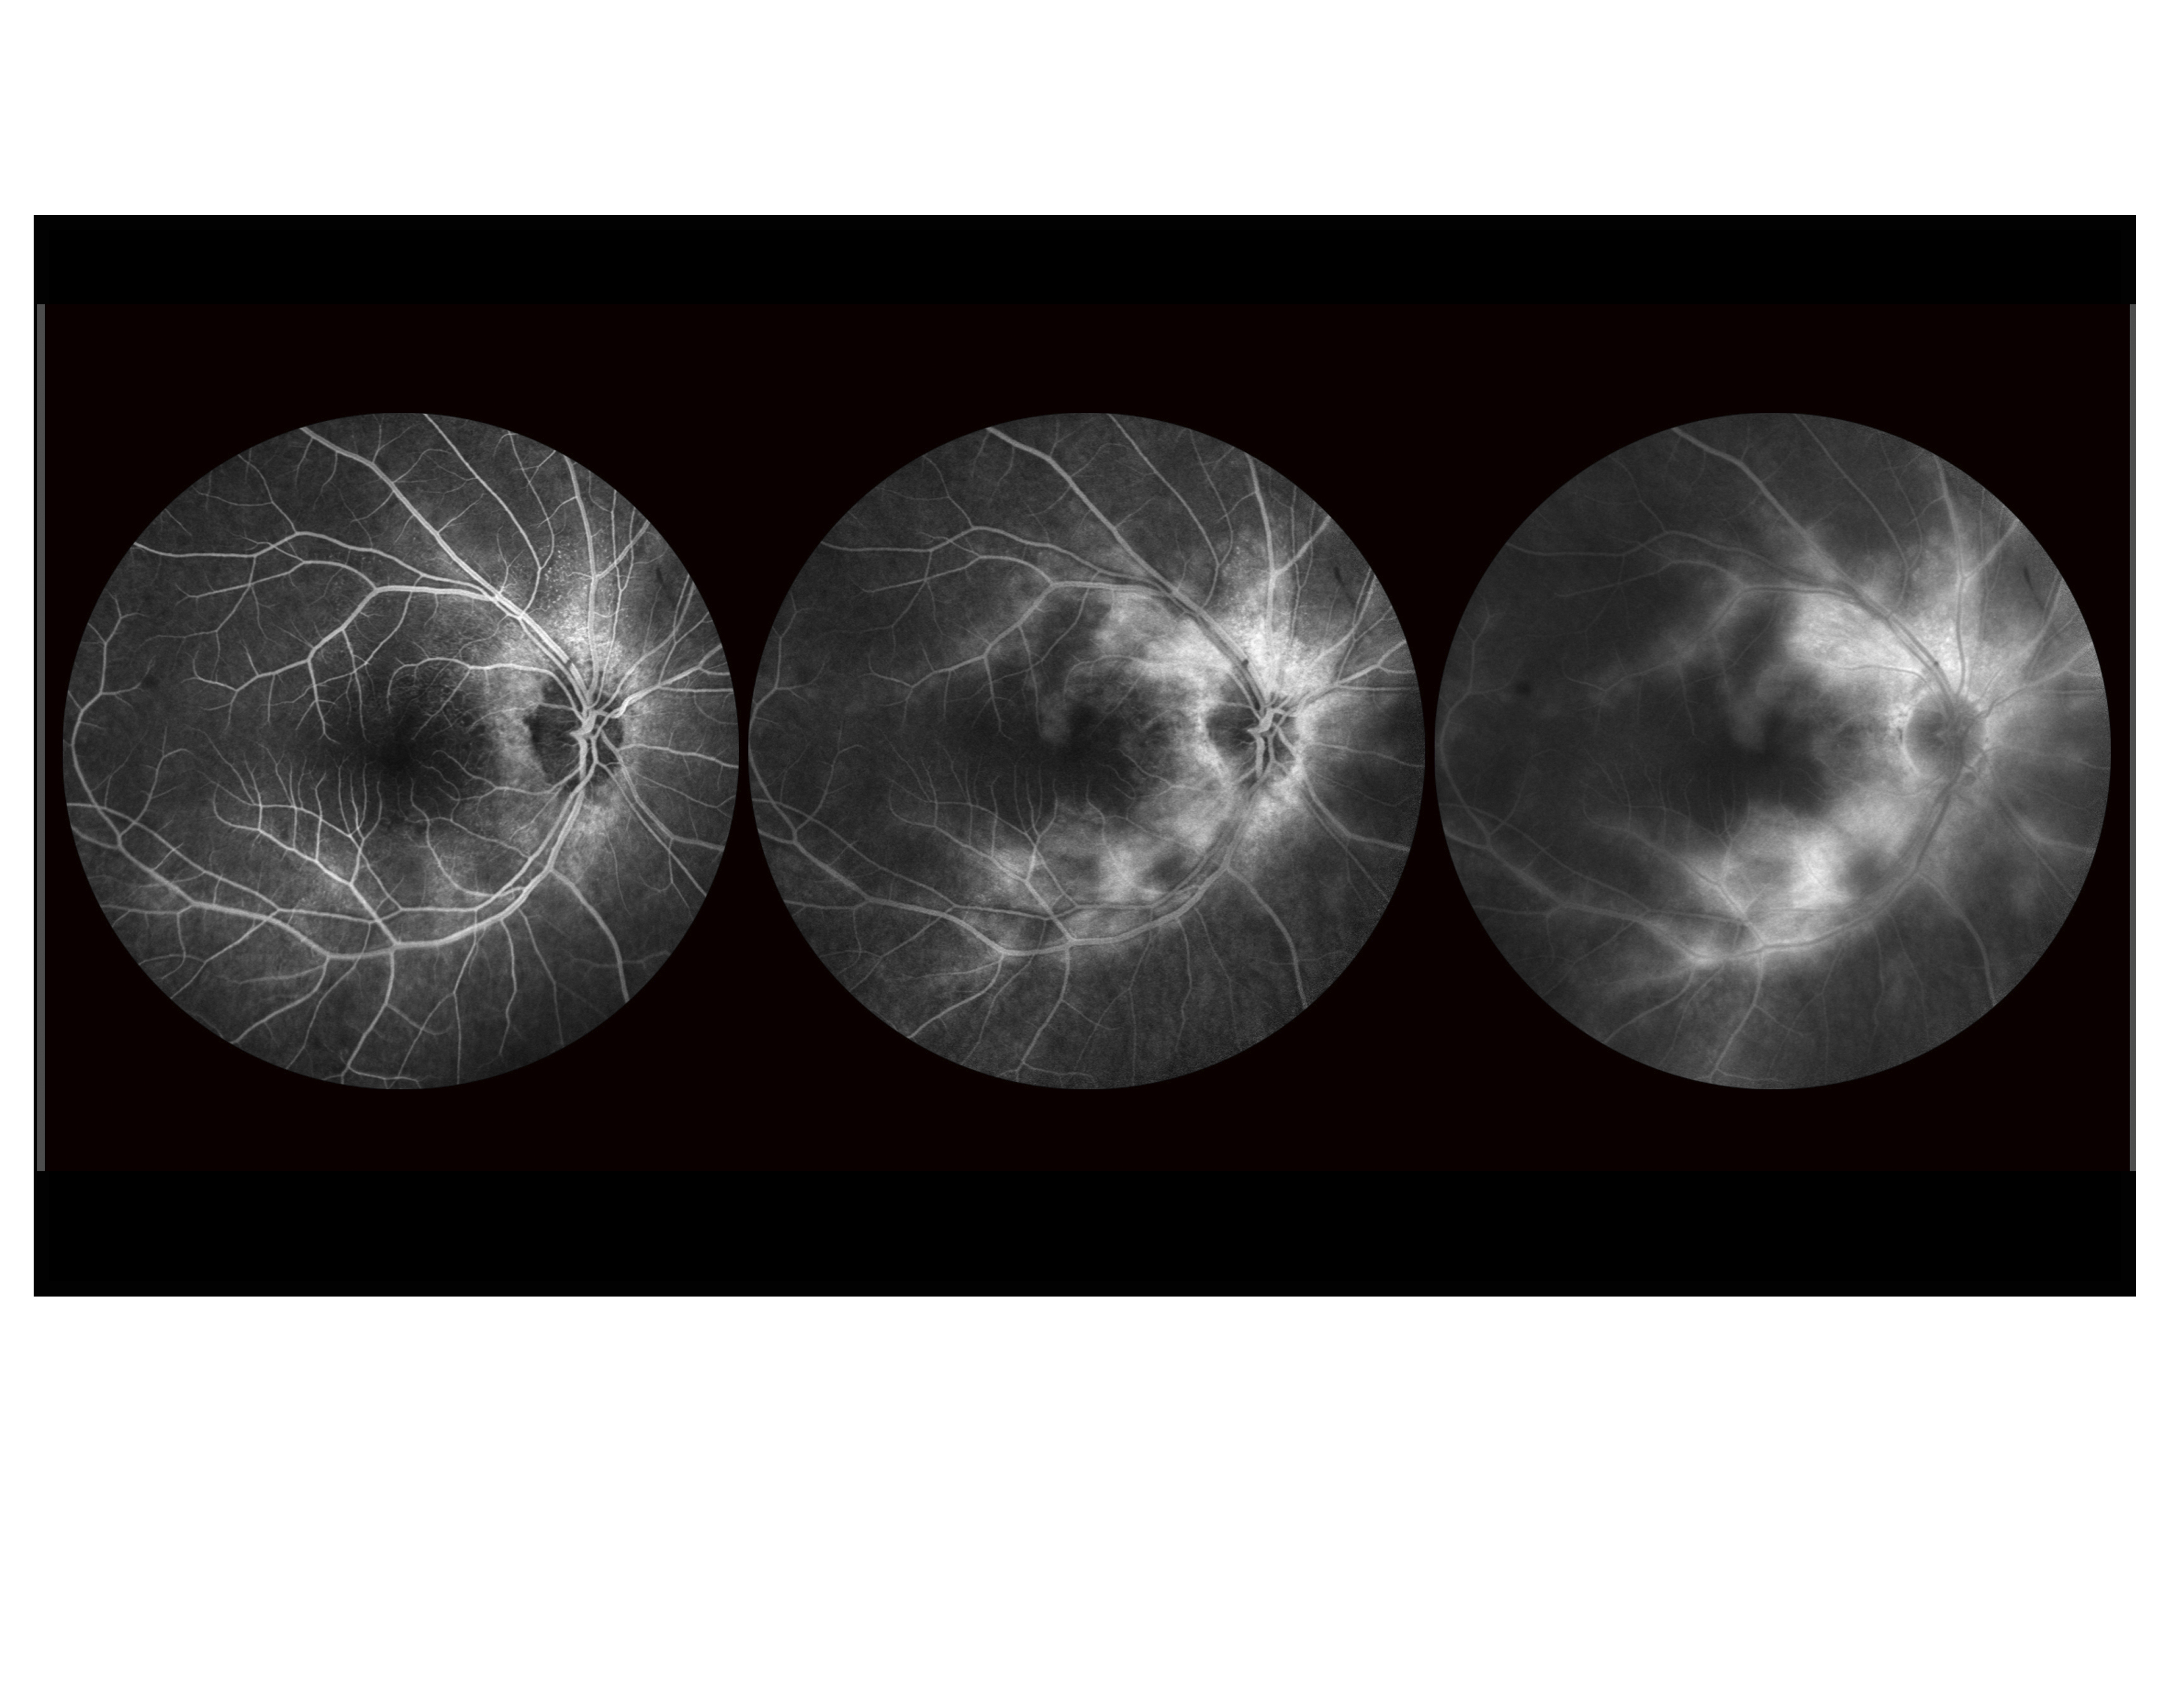

Intermediate Uveitis Presented by Barbara Klemene This photograph received Third Place in the category "Fluorescein Angiography" and was displayed in the 2024 OPS Exhibit. Filed Under Retina OPS Photo